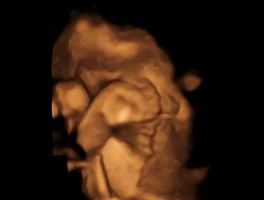

[임신 in 미국] 임신 10개월 (36주) : 성장 초음파 Growth Unltrasound (0) | 2017.03.24 |